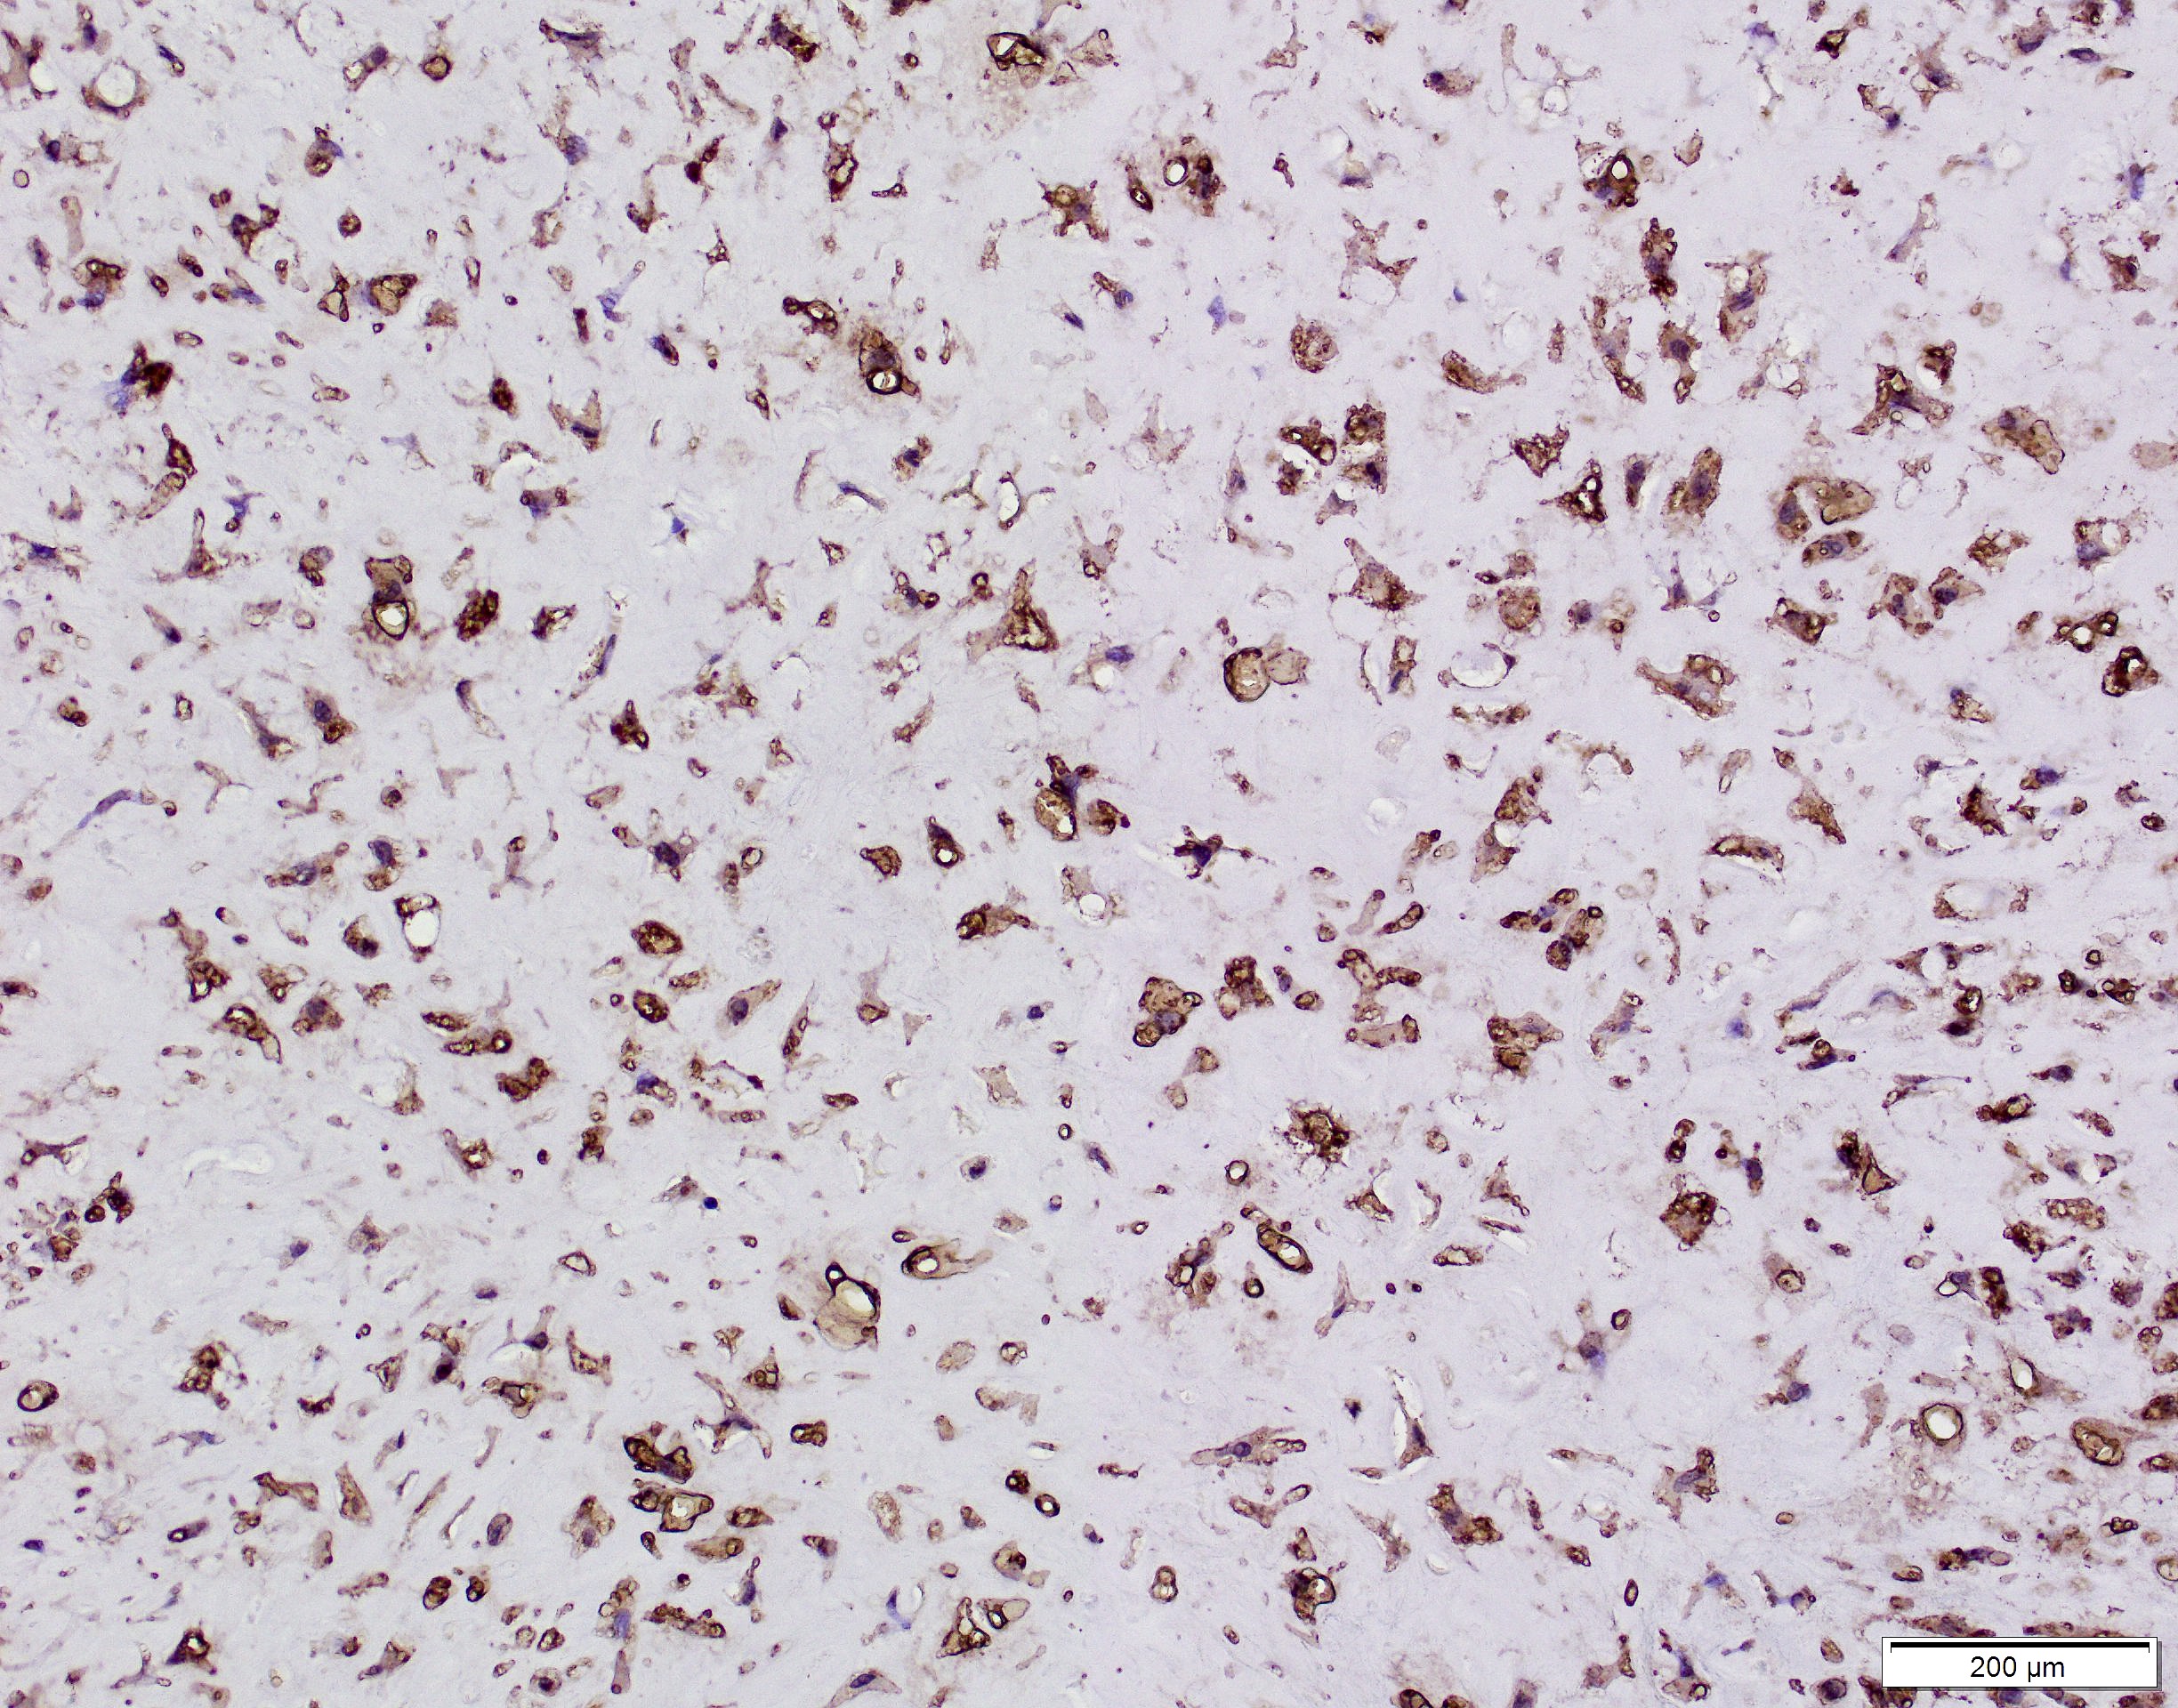

Positive stains

- Glial fibrillary acidic protein (GFAP) ~90% (Head Neck Pathol 2015;9:315)

- S100 protein > 90%

- CD56 and CD57 > 50% (Head Neck Pathol 2015;9:315)

- Authors often attribute the immunodiversity to the pluripotency of the neural crest origin

- Many other markers, such as SMA, p63, cytokeratin, desmin and SOX10, are positive in a subset (< 50%) (Head Neck Pathol 2015;9:315, Int J Surg Pathol 2016;24:586, Oral Surg Oral Med Oral Pathol Oral Radiol Endod 2010;110:e48)

Negative stains

- EMA typically negative